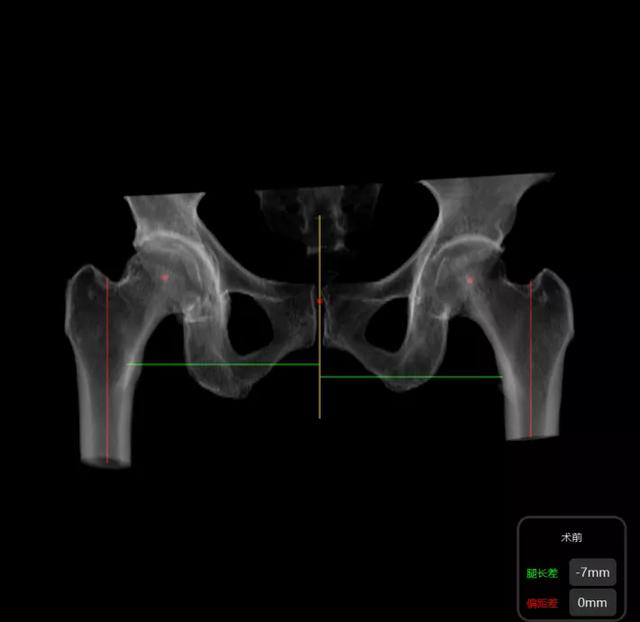

▲ 髋关节置换术前:计算机模拟截骨位置、使用假体的大小和放置的角度。